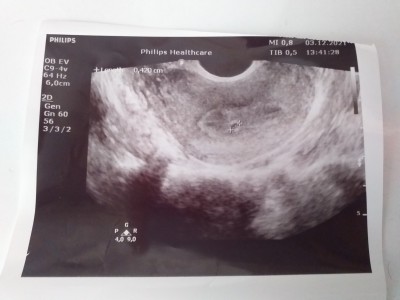

Adet tarihine gore 6+1 doktor karin ultasondan keseyi göremedi alttan baktı ve 4 milim olduğunu geç döllenme olduğunu söyledi sizce normel mi

Gebelik haftası 6+1